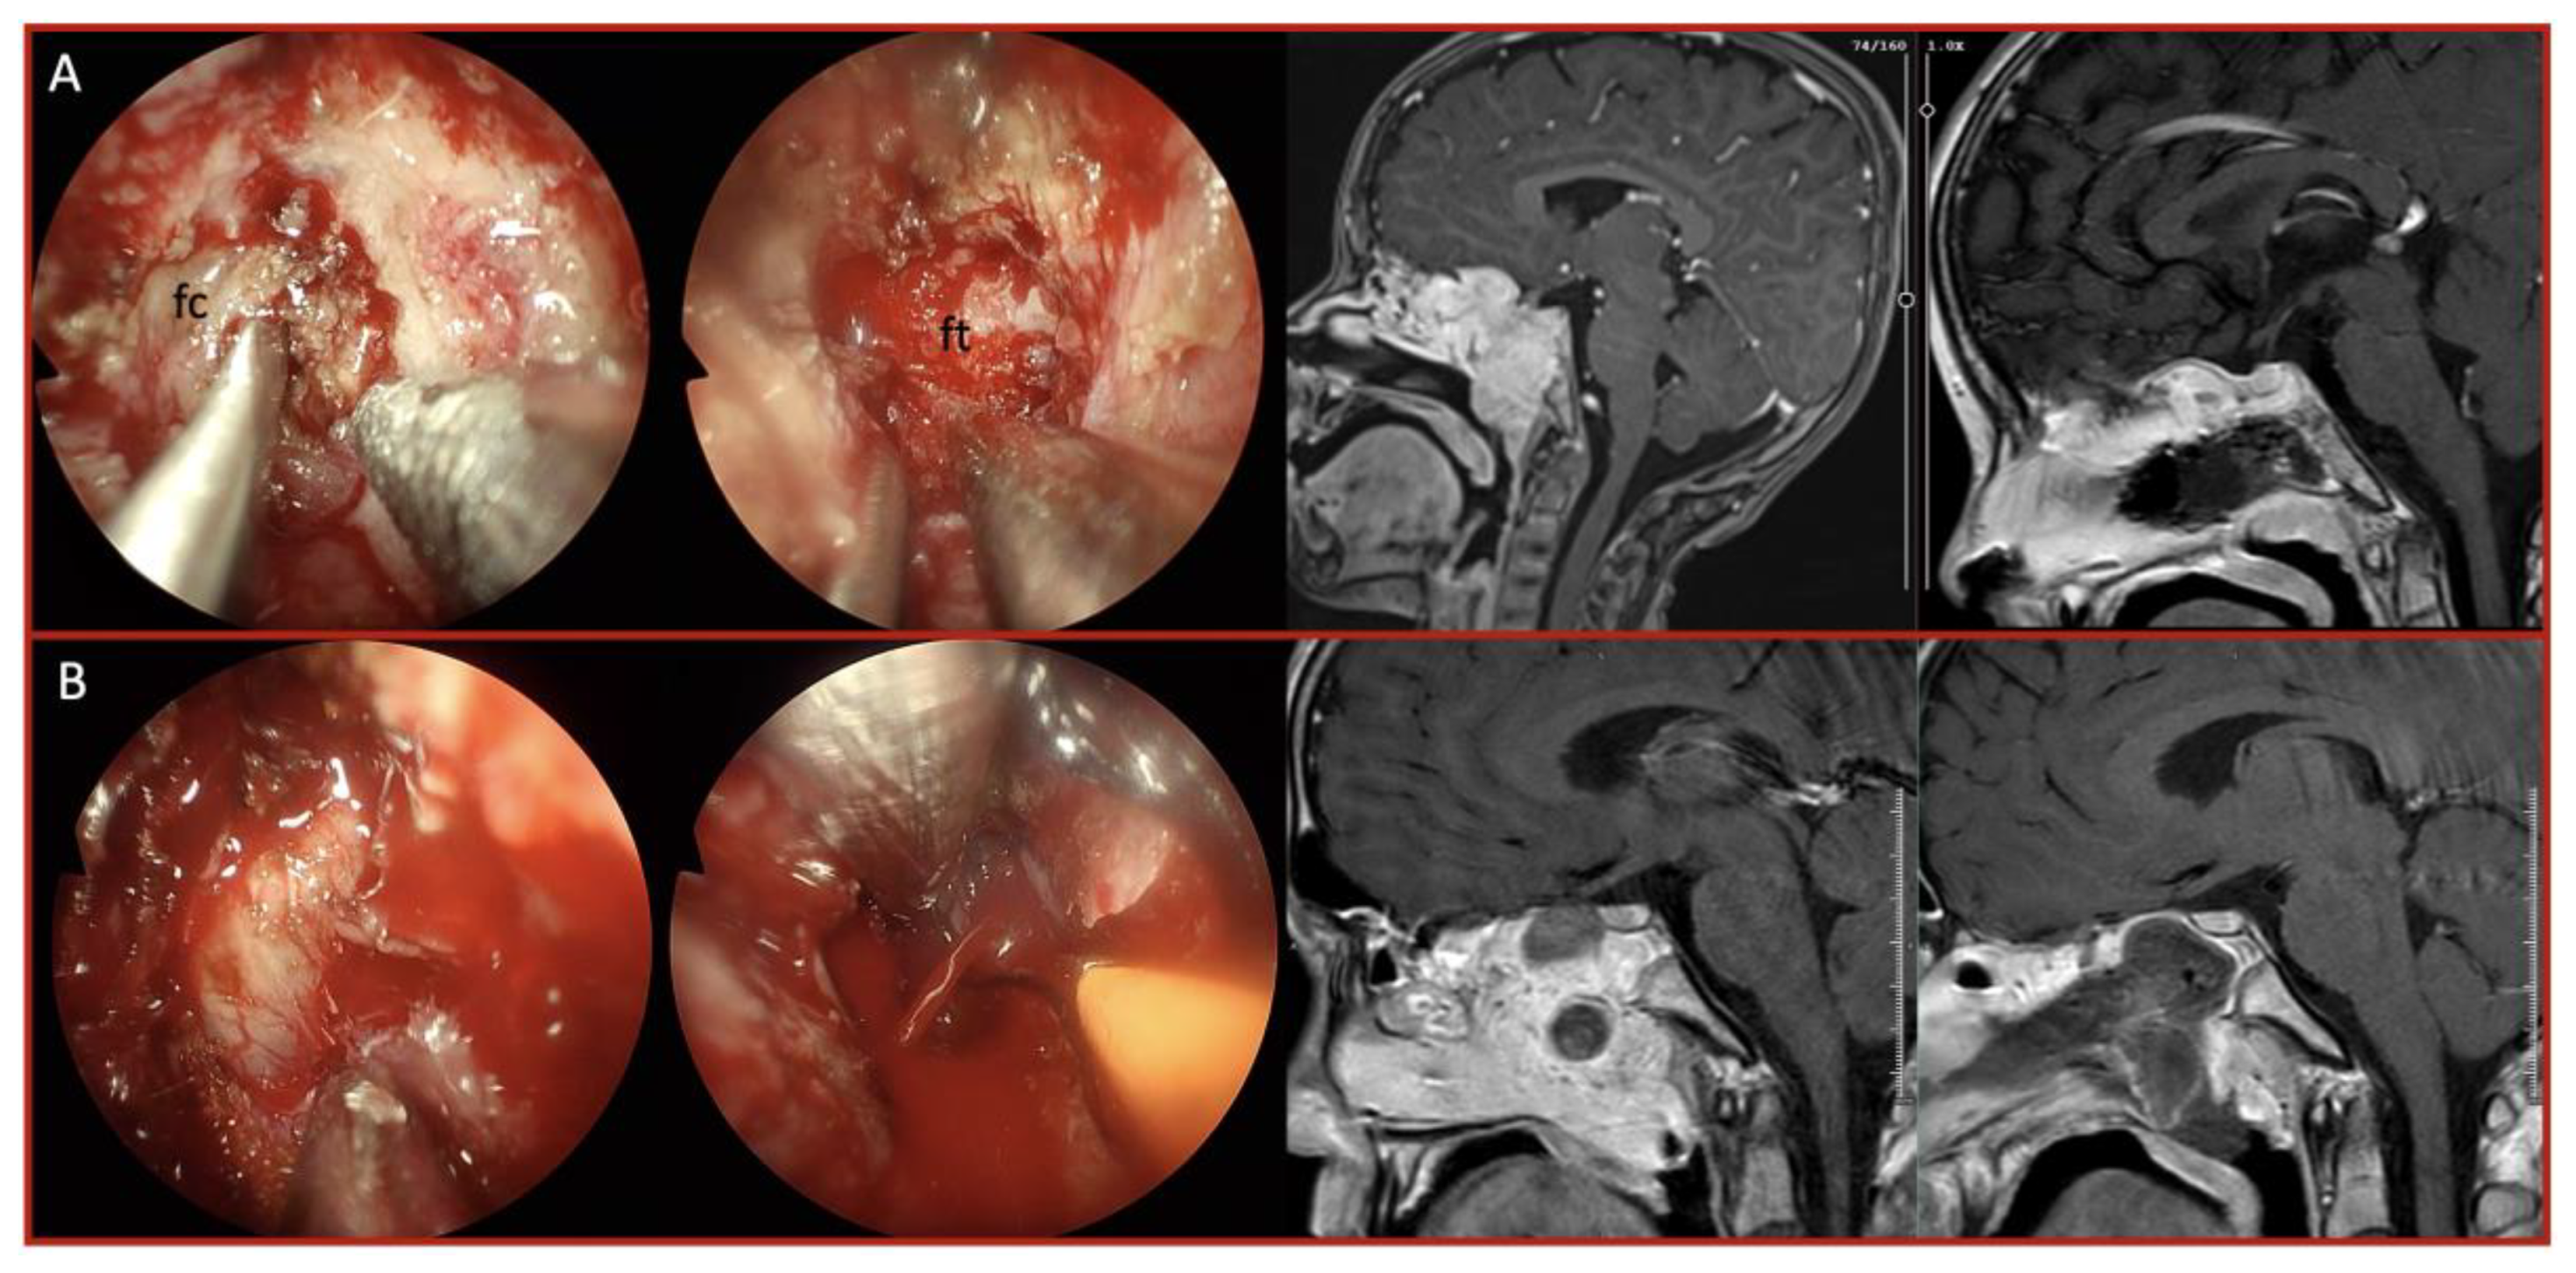

Background: Endoscopic endonasal approach (EEA) has become a well- established approach for skull base pathologies, providing a minimally invasive corridor to access various lesions. While the technique has been extensively studied for common skull base tumors, data on extremely rare pathologies remain limited. Our study aims to present our experience with rare skull base lesions managed via the endoscopic endonasal approach, highlighting the challenges associated with preoperative diagnosis, intraoperative decision-making, and surgical strategy modifications. Methods: A retrospective analysis was conducted on patients who underwent endoscopic endonasal surgery at the tertiary center up to January 2025. Among 6,225 endoscopic endonasal procedures performed, 41 patients with exceptionally rare skull base pathologies were identified. Each tumor type was separately evaluated for differences in resection rates, complication rates, and recurrence patterns. Results: These included 6 pituitary pituicytomas, 5 plasmacytomas, 5 xanthogranulomas, 4 granular cell tumors, 3 giant cell tumors and others. Gross total resection was achieved in 68% of cases, with subtotal resection in vascular or malignant tumors. Intraoperative challenges included unexpected vascularity and fibrotic adhesions. Postoperative CSF leakage occurred in 7%, and recurrence was observed in 17%, mostly in malignant or partially resected tumors. No intraoperative mortality was recorded. Tailored adjuvant treatments ensured durable disease control in most patients. Conclusions: Even in highly experienced centers, rare skull base pathologies pose unique diagnostic and surgical challenges. The discrepancy between preoperative and intraoperative findings often necessitates real-time strategic adaptations. In these rare cases, for optimizing patient outcomes requires a comprehensive understanding of skull base anatomy, flexibility in surgical planning, readiness for sudden strategy modifications, and a multidisciplinary approach.

| Tumor Type | No. of Cases | Consistency / Vascularity | Extent of Resection | Adjuvant Therapy / Recurrence |

|---|---|---|---|---|

| Pituicytoma | 6 | Firm, highly vascular capsule | GTR/STR (5/1) |

No recurrence, no adjuvant |

| Plasmacytoma | 5 | Soft, moderately vascular | GTR/STR (3/2) |

RT + chemo; 2 recurrences |

| Xanthogranuloma | 5 | Fibrotic, adherent | GTR | No recurrence |

| Granular cell tumor | 4 | Soft intense | GTR | Gamma Knife (case-based) |

| Giant cell tumor | 3 | Highly vascular | GTR Pre-operative embolization |

Denosumab Fully controlled |

| Germinoma | 2 | Soft, Vascular capsule | STR | Chemo + RT; 1 recurrence |

| HPC | 2 | Hypervascular | STR | RT; 1 recurrence |

| LCH | 2 | Firm, fibrotic | GTR/STR (1/1) |

Systemic chemo; stable |

| Malignant epithelial | 2 | Adherent, fibrotic | STR | 1 Recurrence |

| Spindle cell oncocytoma | 2 | Firm, vascular | GTR/ STR 1/1 |

1 Gamma Knife |

| Others (each 1) | 10 | Varied | Varied | Case-specific |